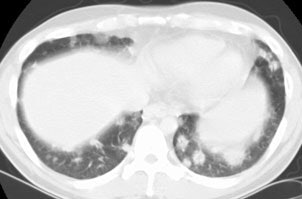

BOOP presenting with pulmonary nodules:

The patient below presented with complaints of cough, malaise, and a low-grade fever. The chest radiograph revealed some patchy left lower lobe airspace disease and vague nodular shadows- particularly in the lower lung zones. A chest CT was performed and demonstrated multiple nodular airspace abnormalities with variable margins. The lesions did not improve despite antibiotic therapy and all cultures were negative. Click images to enlarge. |

Open lung biopsy confirmed the diagnosis of BOOP. Following institution of therapy with steroids the lung lesions resolved. Click images to enlarge.